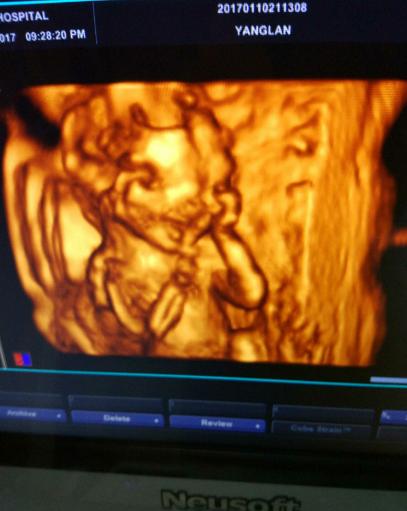

朋友怀孕几个月了,每隔一段时间就去检查。迫切地想知道肚子里是个“小鸡妞”,还是“小鸡仔”。前两天又去医院做了唐氏筛查,医院刚好新进了四维机,说是能看到辨别宝宝的性别,朋友兴奋的不得了,于是赶快做了一个检查。第一次看到宝宝动,好激动,医生很仔细的帮看,老公也在看,医生看大腿小鸡鸡好明显,我老公说小鸡鸡耶,医生说看到没有凸起来的那个就是小鸡鸡,朋友说:“听到自己肚子里是个小鸡仔的时候,眼泪不自觉地流了下来。”